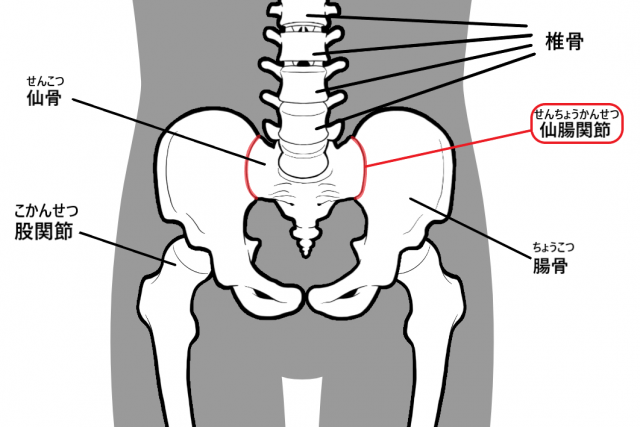

骨盤を構成する骨に腸骨と仙骨という骨があります。

その仙骨の上に椎骨という骨が積み木のように縦積みに連なって背骨を形成しています。

仙骨を腸骨という骨が両側から挟みこむ関節を仙腸関節と言い、上半身と下半身をつなぐ重要な関節になります。